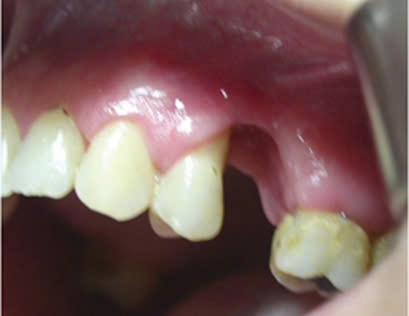

Hình 3: Xương ổ răng bị tiêu, lợi bị hoại tử ở vùng răng 13-14.

Hình 4: Xương ổ răng và nhú lợi vùng răng 37 bị hoại tử do arsenic7

Báo cáo những trường hợp lợi bị hoại tử do sử dụng arsenic băng thuốc trong buồng tủy thường liên quan tới những răng phải điều trị nội nha có tổn thương sâu mặt bên (xoang II).